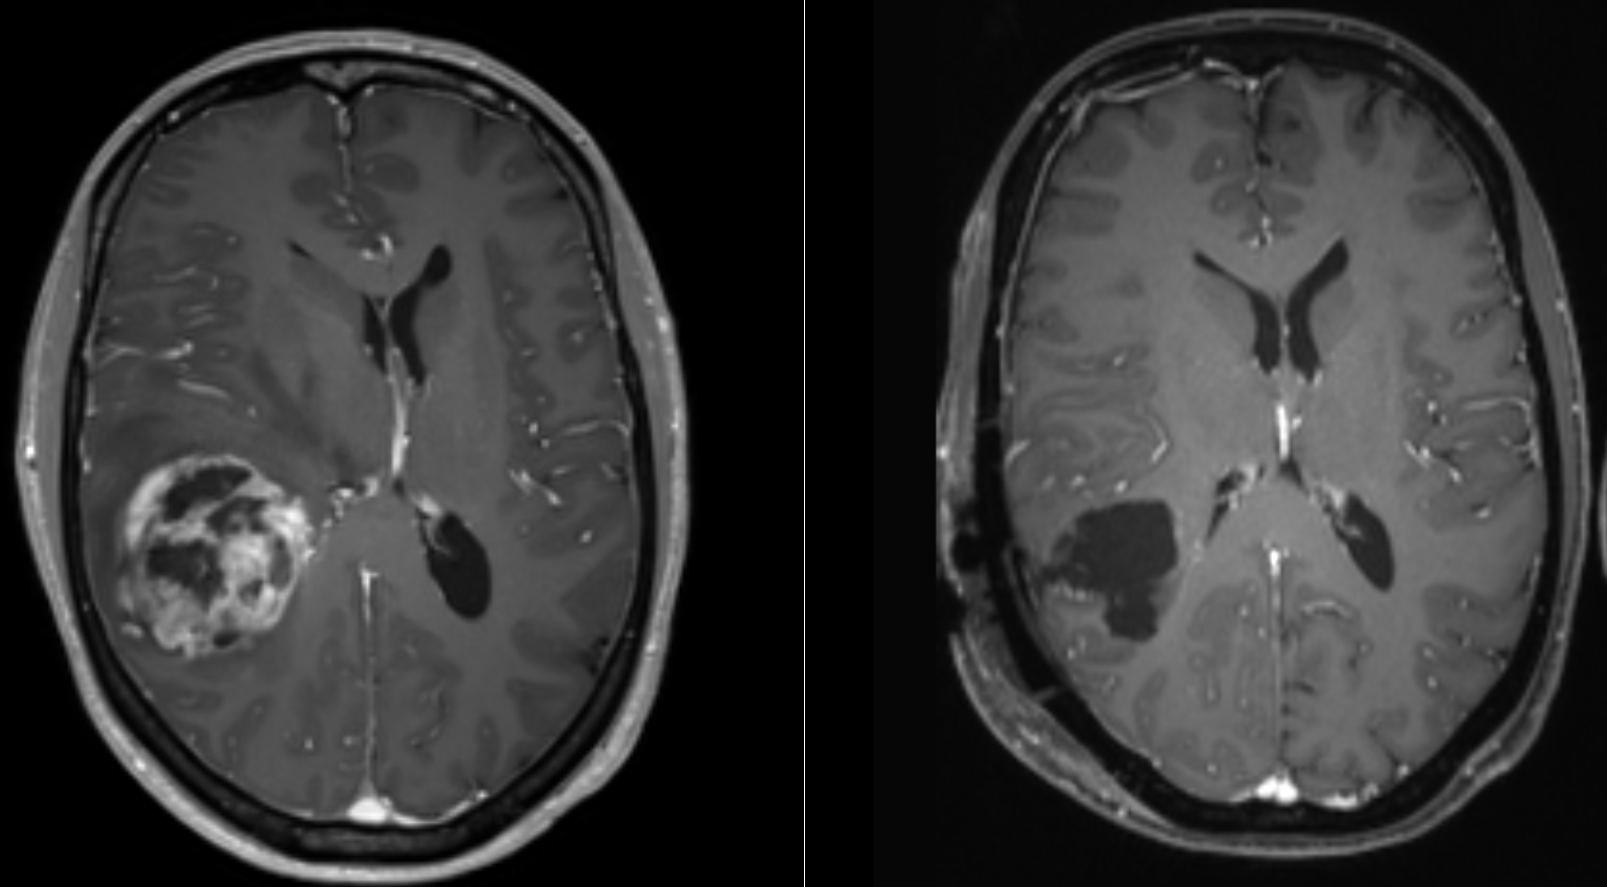

MRI로 볼 때, 교모세포종은 종종 환상 강화 병변으로 나타난다. 그러나 농양, 전이, 종괴성 다발성 경화증 등도 유사한 모습을 보일 수 있어 이 모습만으로는 특정할 수 없다.[61] CT 또는 MRI에서 교모세포종으로 의심되는 질환의 확진은 정위 생검 또는 종양 절제 및 병리적 확인을 위한 개두술이 필요하다. 종양 등급은 종양의 가장 악성인 부분에 기반하므로, 생검 또는 아전 절제술은 병변의 등급을 낮게 평가하는 결과를 초래할 수 있다.

; MRI

: T1 강조 영상에서는 종양이 약간 저신호역, T2 강조 영상에서는 종양과 그 주변의 뇌부종이 고신호역이 된다. 가돌리늄을 사용한 조영 MRI에서는 종양의 변연이 고신호역이 되는 한편, 종양 내부는 괴사 등을 반영하여 저~고신호역이 뒤섞인 영상이 되는 경우가 많다. 이 소견을 링 강화라고 칭한다. 또한, 링 강화는 교모세포종에 특이적인 소견이 아니며, 뇌농양, 전이성 뇌종양 등이 감별로서 거론되는 경우가 많다.

- MRI: T1 강조 영상에서는 종양이 약간 저신호역, T2 강조 영상에서는 종양과 그 주변의 뇌부종이 고신호역이 된다. 가돌리늄을 사용한 조영 MRI에서는 종양의 변연이 고신호역이 되는 한편, 종양 내부는 괴사 등을 반영하여 저~고신호역이 뒤섞인 영상이 되는 경우가 많다. 이 소견을 링 강화라고 칭한다. 또한, 링 강화는 교모세포종에 특이적인 소견이 아니며, 뇌농양, 전이성 뇌종양 등이 감별로서 거론되는 경우가 많다.

- MRI: T1 강조 영상에서는 종양이 약간 저신호역, T2 강조 영상에서는 종양과 그 주변의 뇌부종이 고신호역이 된다. 가돌리늄을 사용한 조영 MRI에서는 종양의 변연이 고신호역이 되는 한편, 종양 내부는 괴사 등을 반영하여 저~고신호역이 뒤섞인 영상이 되는 경우가 많다. 이 소견을 링 강화라고 칭한다. 링 강화는 교모세포종에 특이적인 소견이 아니며, 뇌농양, 전이성 뇌종양 등이 감별로서 거론되는 경우가 많다.